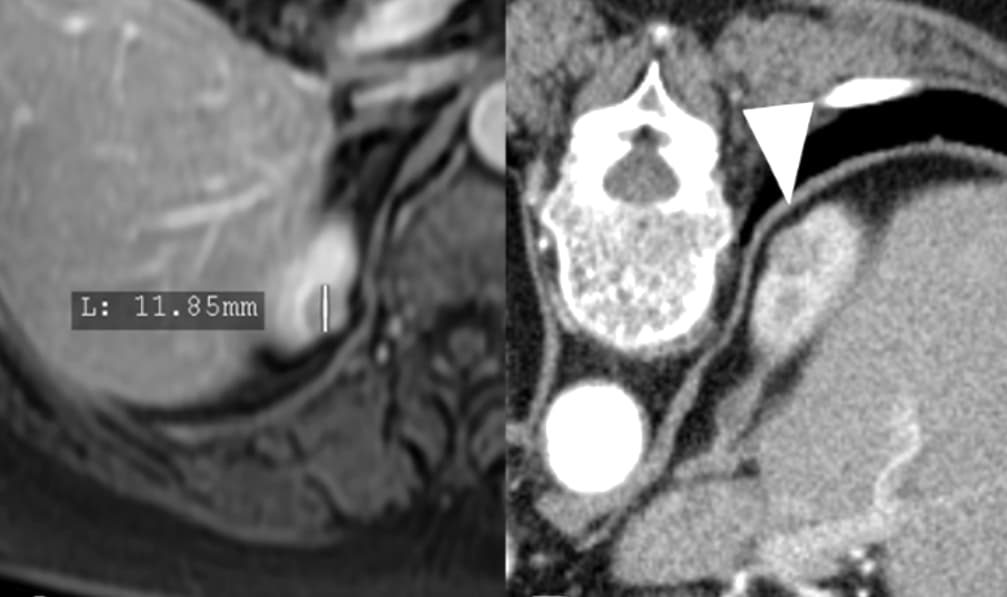

Les techniques percutanées d’ablation percutanée, thermique ou radiothérapeutique, de tumeurs rénales gagnent du terrain mais les recommandations varient selon les régions. Un article publié dans la Revue European Radiology fait une synthèse des recommandations à travers le monde. Et celles-ci ne sont pas homogènes, la chirurgie étant plutôt préconisée en Europe alors que l’ablation percutanée se généralise aux USA.

Une vaste étude danoise montre qu’une procédure mini-invasive d’ablation est aussi efficace que la chirurgie pour traiter les petits cancers du rein, avec une récupération plus rapide et moins de complications. Les résultats de l’étude ont été publiés récemment dans la Revue Radiology.